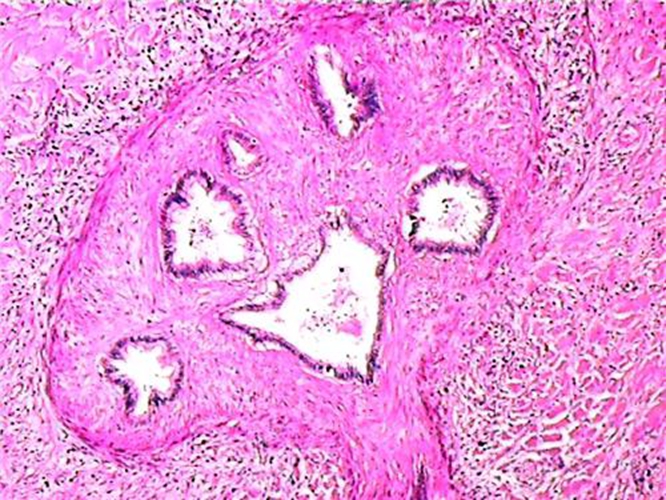

肝內膽管癌